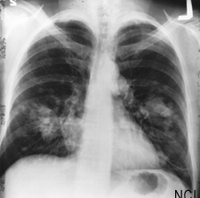

Published August 4, the reduced lung-cancer mortality with low-dose computed tomographic (CT) screening study found a 24.2 percent increase in the detection of lung cancer using low-dose CT over chest X-ray alone. The study, which enrolled 53,454 persons at high risk for lung cancer at 33 United States medical centers, also found a 20 percent reduction in mortality from lung cancer in patients who were screened with a low-dose CT.

"This is the first time that we have seen clear evidence of a significant reduction in lung cancer mortality with a screening test in a randomized controlled trial. The fact that low-dose helical CT provides a decided benefit is a result that will have implications for the screening and management of lung cancer for many years to come," says Christine Berg, M.D., the National Cancer Institute project officer for the study.